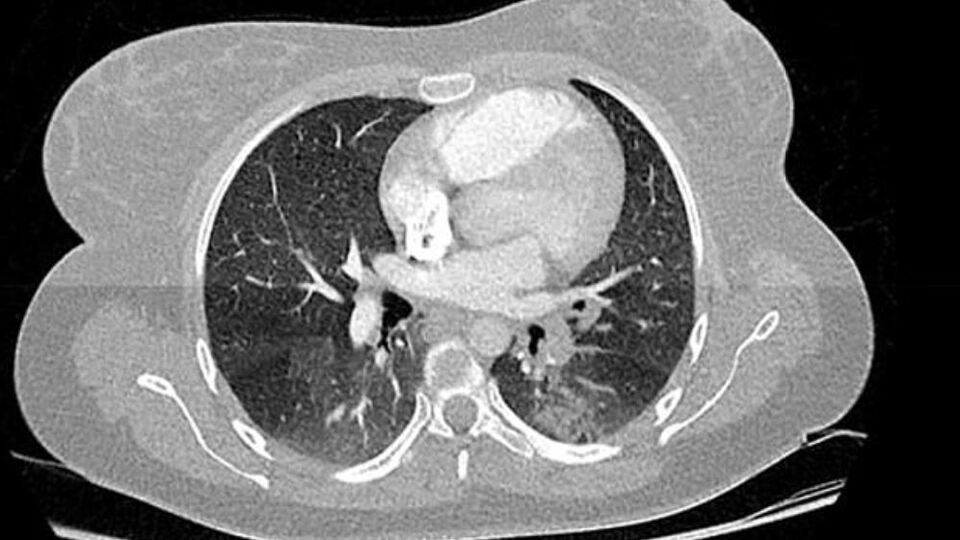

Fransa'nın Haut-Rhin bölgesindeki Colmar kentinde bulunan Albert Schweitzer Hastanesi'nden Dr. Michel Schmitt ve ekibi, 2019´un son aylarında çekilen binlerce göğüs filmini incelerken koronavirüs ile benzer iki bulgu belirledi.

Dr. Schmitt ve ekibinin 16 - 18 Kasım 2019 tarihleri arasında çekilen göğüs filmlerini analizi sırasında yaklaşık 2 bin 500 röntgende koronavirüs bulgularına benzer bulgular rastlandığı ifade edildi. Sonuçların henüz çıkarılamayacağını ve ekibinin virüsün yayılmasını haritalamak için Ekim'e kadar uzanan X-ışınlarına bakacağını söyleyen Dr. Schmitt , "Geleceği ancak geçmişi anlarsak yönetebiliriz. Bugün bu salgını açıkça anlamıyoruz. Bu hükümetin yönetim stratejisini tamamen değiştirebilir" dedi.